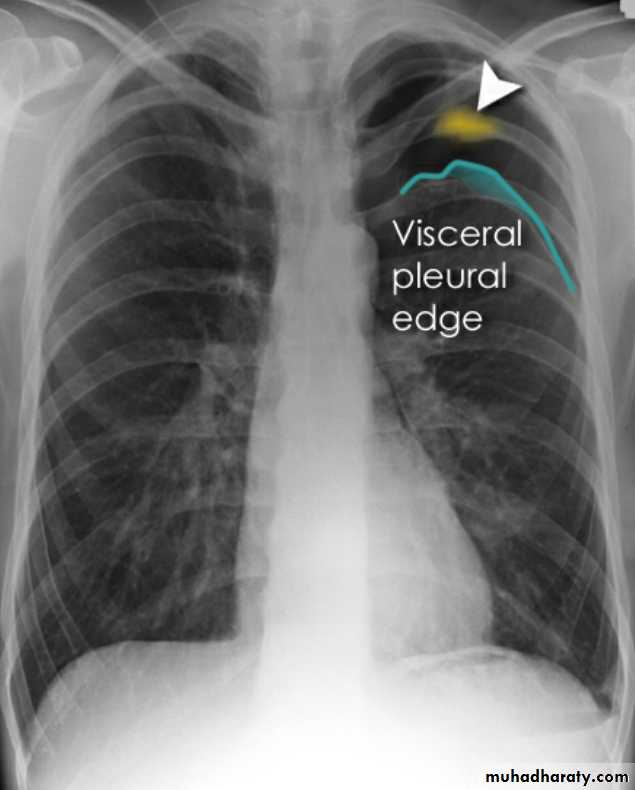

Radiolucent area devoid of lung markings in the upper left lung

Visible viseral pleural edge as very thin sharp white lineRadiolucent area devoid of lung markings in the upper left lung

Visible viseral pleural edge as very thin sharp white linePneumothorax

Radiolucent area devoid of lung markings in the periphry of the right lung with visible viseral pleural edge